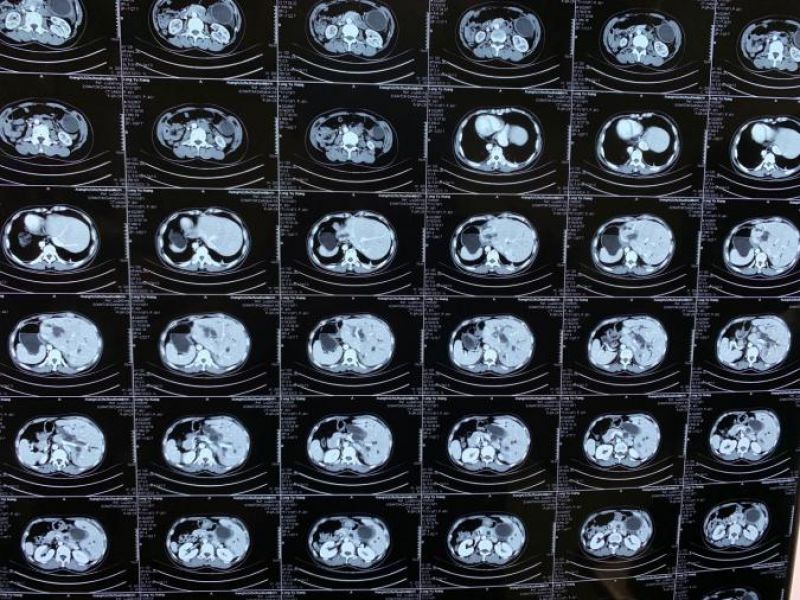

术前CT